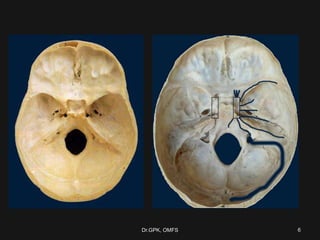

6Dr.GPK, OMFS

• 6.

• 7.